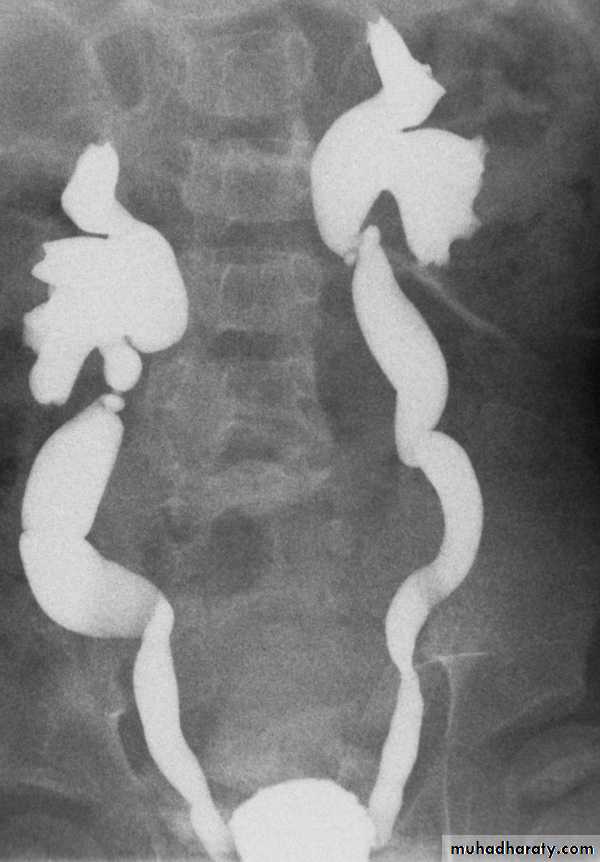

*Bilateral megaureter